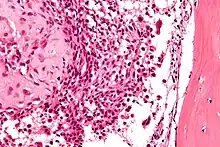

| Micrograph of a chondroblastoma. H&E stain. | |

Chondroid differentiation is a common feature of chondroblastoma.[1][4][6] A typical histological appearance consists of a combination of oval mononuclear and multi-nucleated osteoclast-type giant cells.[1][3][4] However this is not a prerequisite for diagnosis, as cells with epithelioid characteristics have been observed in lesions of the skull and facial bones.[4] A "chicken-wire" appearance is characteristic of chondroblastoma cells and is the result of dystrophic calcification that may surround individual cells.[1][5] Although, calcification may not be present and is not a prerequisite for diagnosis.[1][3][4] Mitotic figures can be observed in chondroblastoma tissue but are not considered atypical in nature, and therefore, should not be viewed as a sign of a more serious pathology.[1][4] There is no correlation between mitotic activity and location of the lesion.[4] Furthermore, the presence of atypical cells is rare and is not associated with malignant chondroblastoma.[1][6] There are no discernible histological differences observed when comparing the aggressive form of chondroblastoma that can cause recurrence or metastases with its less aggressive, benign, counterpart.